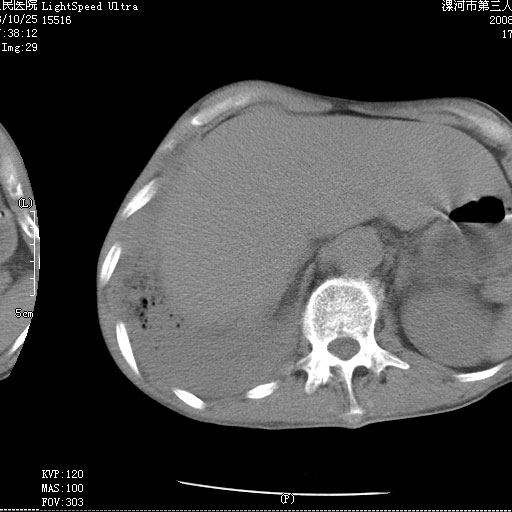

m 老年 发烧、呼吸困难,慢支、肺气肿多年;记的那次是下午大概17:38做的,晚上窒息死亡。

上面的层面就慢性支气管炎肺气肿、肺大泡,别的没有什么、也就不传了。

当时我怀疑:1、阻塞性肺不张早期 2、肺脓肿早期,望老师们发表意见

1、右侧脓胸;2、copd;

3、细支气管肺泡癌可以排除,病变以斜裂为界,呈大片状高密度影,内可见多发小气泡,表明有产气杆菌感染所致,内无明显的支气管“枯树枝征”表现,再结合其临床改变(细支气管肺泡癌临表表现重、影像表现轻)所以不符合细支气管肺泡癌(炎症型)的改变。

按肺叶分布,考虑肺不张

病变按肺叶分布,病变内可见多个小空腔影,未见充气支气管影,中间段支气管管腔肺窗示密度欠均匀,下肺支气管分叉处基底段支气管隐约可见,未见明显狭窄,中叶支气管通畅,

考虑:阻塞性肺炎伴小脓肿形成可能性大。(痰栓可能性大)

右下肺实变,内有弥漫分面小气泡而无支气管征,叶间裂前移,呈臌大之形,而无收缩之状,兼纵隔稍左行移,故。不支持不张,倒支持大叶肺叶,如楼上所说,小气泡不象残留之肺,不可以考虑产气菌感染吗。

阻塞性肺炎,肺脓肿形成。依据,右下支气管不通,大片实变形内可见小气泡。不支持肺不张。